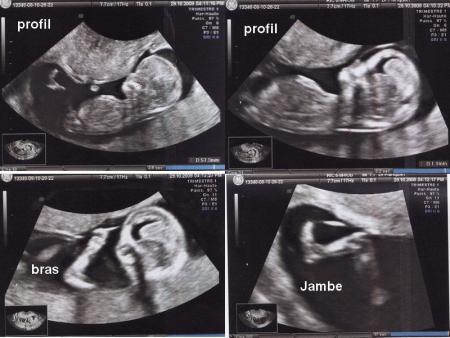

voila ma ptite quéquéte Jade

avec bcp de retard voici le compte rendu de ma visite du gygy le 8 decembre 2008

j'étais à 18 SA +1

tension 12/ 6 col fermé

poid +7kg400 depuis le début :(

bébé va bien prochaine visite le 5 janvier 2009

et prochaine echo le 6 janvier 2009

j'ai mis seulement qq clichés d'echo j'allais pas tout mettre j'ai 3 pages et ca revient souvent au meme